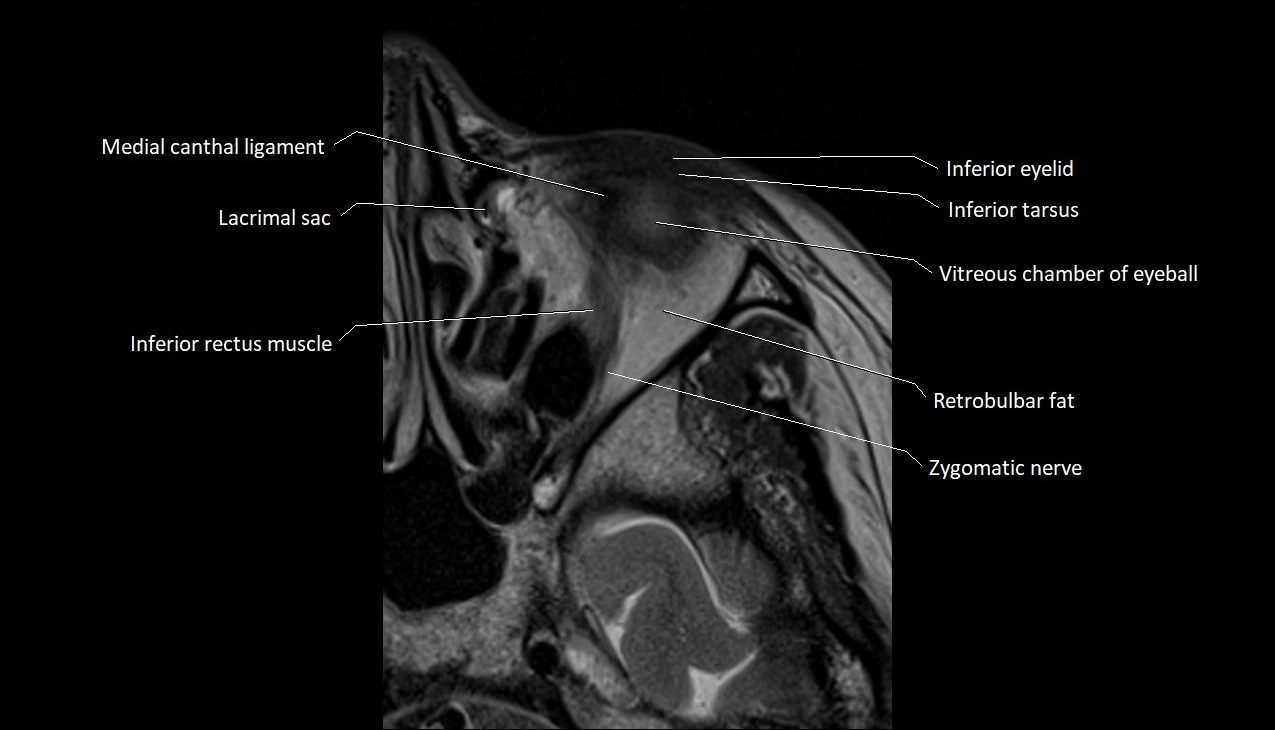

- Inferior eyelid

- Inferior rectus muscle

- Inferior tarsus

- Medial canthal ligament

- Retrobulbar fat

- Vitreous chamber of eyeball

- Zygomatic nerve